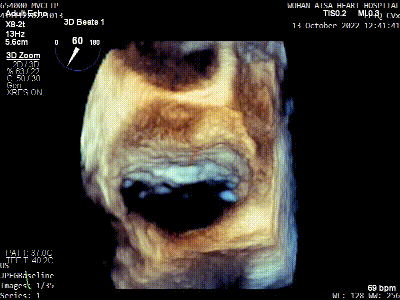

术前TEE评估

原发性二尖瓣反流(DMR),后叶P3区脱垂,反流程度4+,EROA 0.40cm2、RV 39ml;二尖瓣瓣口面积5.37cm²;二尖瓣前叶(A3)长度14.0mm,二尖瓣后叶长度(P3)长度12.2mm,脱垂宽度8.2mm,脱垂高度1.4mm;RA 2.9cm ,LA 3.6cm,左室射血分数LVEF56%,术前测量最大房间隔穿刺高度4.0cm

将MitraClip™XTR送入左房,由于左房太小,在达到骑跨过程中反复推进回撤CDS和稳定器,同时旋转SGC,达到骑跨的同时,保证Clip头端游离,且SGC在左房有深度。旋转M,同时顺时针往后旋转SGC借高度,使Clip垂直二尖瓣环平面,由于穿刺高度不够,Clip直接进入左室,这意味着操作要十分小心,左室组织复杂,稍有不慎将会造成组织损伤。使用A/P Konb中“A”旋钮借高度。确认垂直后,直接在左室打开Clip,3D外科视角,逆时针旋转使Clip夹臂处于11点-5点方向,回拉稳定器,使Clip处于3区脱垂区域,用“+/-”Knob中的“-”旋钮,使Clip更往后叶的同时增加操作高度,抓捕脱垂的瓣叶,关紧Clip后,反流从4+降低至0级,平均跨瓣压差2mmHg,左右肺静脉逆流均改善。前后叶活动度降低,后叶插入长度9mm,前叶插入12mm, 确认稳定性后释放Clip。释放后,即刻效果十分满意,手术圆满结束。